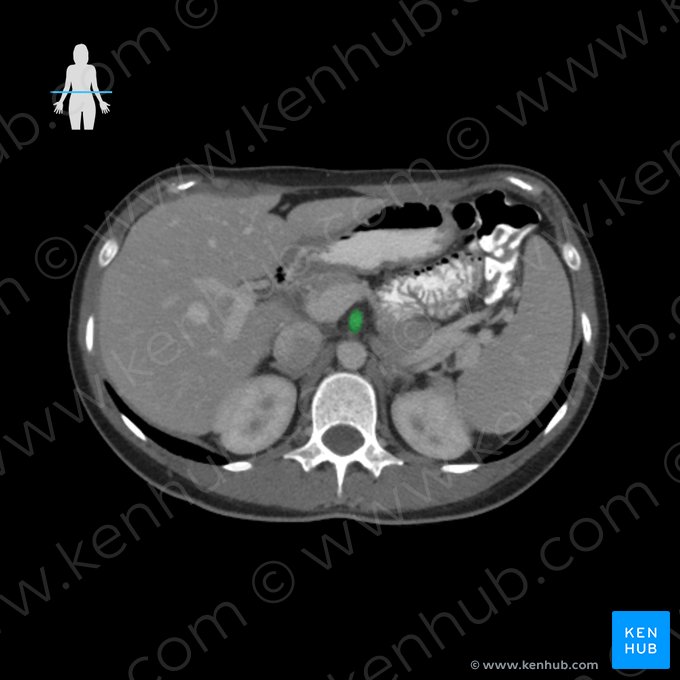

Digestive system and abdominal viscera (CT)

Together with x-ray, CT is a method of choice for examining abdominopelvic anatomy. CT clearly visualizes bone, soft tissue, air, fat and fluids, making abdominal CT a powerful tool in discovering all sorts of abdominal pathology. It is indicated in most of the cases of clinically unclear abdominal pain.

For the sake of clinical examination completeness, it’s necessary to film the entire abdomen of a person at many lumbar vertebral levels. This gives us a stack of abdominal CT scans for examination. To get the full picture of abdominal anatomy, we move through the slices from cranial to caudal while examining structures from their beginning to end. For our assessment, we take a systems approach to the abdominal viscera, primarily dedicating attention to the gastrointestinal tract, examining the patency and general appearance of the digestive tube. For this, we often use contrast agents which are seen as bright white aggregations within the hollow organs. Moreover, one should assess the appearance of the solid organs of the abdomen, namely the liver, pancreas, kidneys, spleen and suprarenal glands.

Browse through these 8 abdominal CT slices and try to assess the anatomy of the digestive system and abdominal viscera.